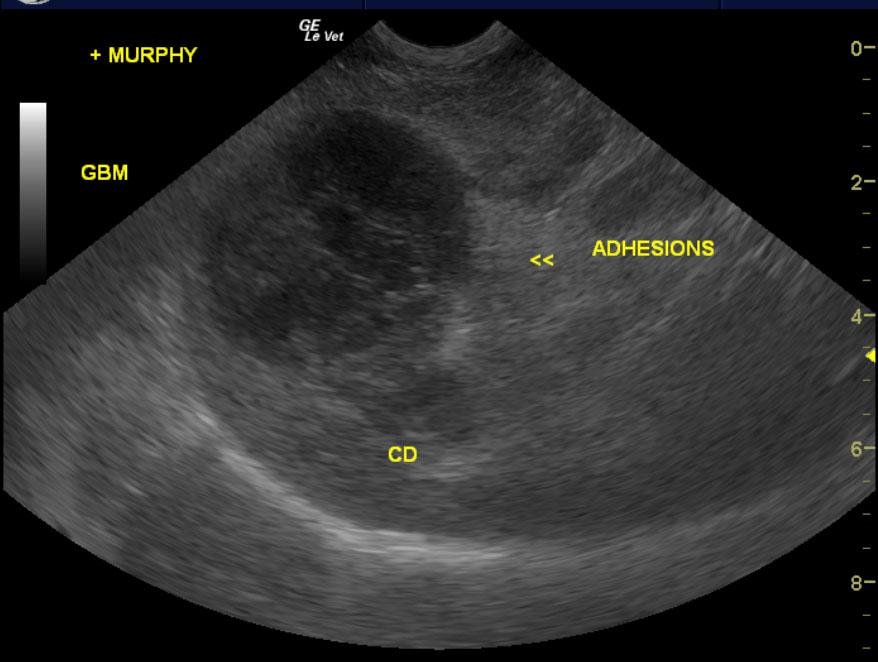

An 11-year-old intact female Cairn terrier dog was presented on emergency at RDVM for vomiting bile for 24 hours. Abnormalities on physical examination were lethargy, severe dental disease, prominent popliteal lymph nodes, and a tense abdomen and prominent liver on palpation. CBC and blood chemistry showed marked leukocytosis, neutrophilia, monocytosis, eosinopenia, thrombocytosis, elevated total proteins, hyperglobulinemia, markedly elevated ALP activity, hyperbilirubinemia, and mild hypercholesterolemia. On abdominal radiographs gas in the stomach and hepatomegaly were evident. The patient was treated with IV fluids, Ampicillin, Baytril, Famotadine, Cerenia, and Buprenex.